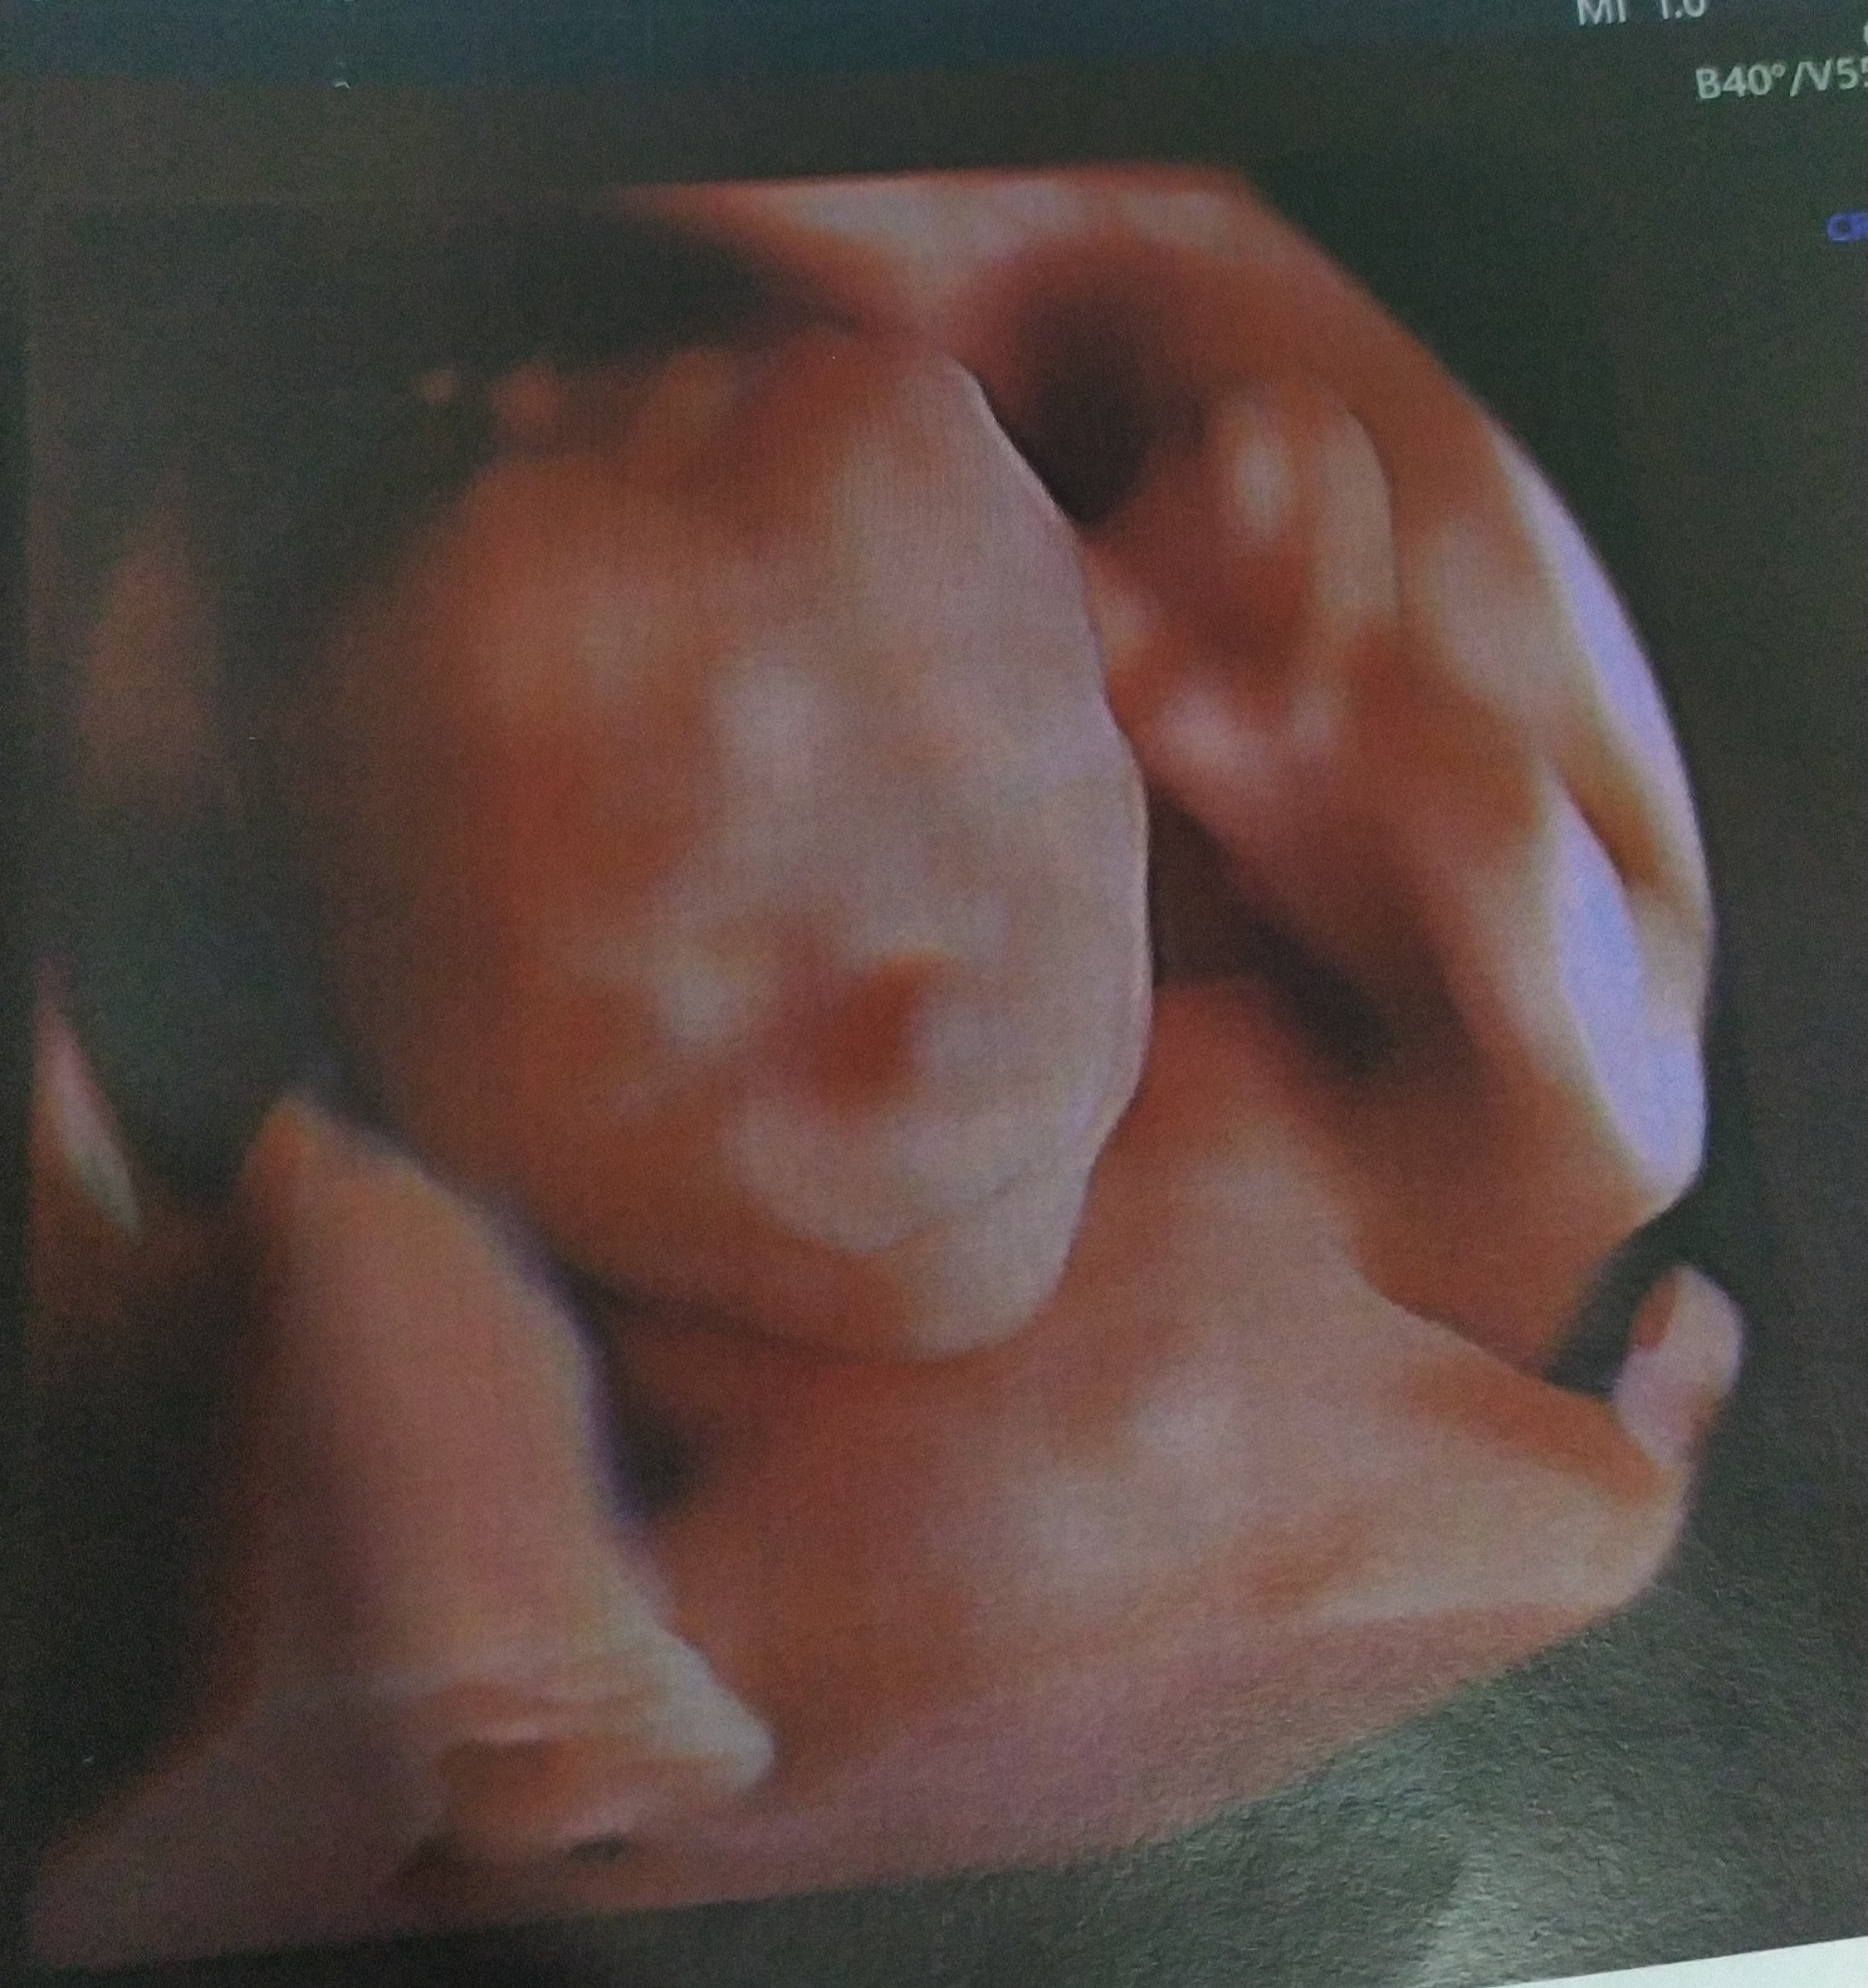

Haha to ufoludekWow wow wow! Ale świetne zdjęcie. Gratuluję udanej wizyty

Teraz możesz poszaleć z ciuszkami jak już wiadomo, że na 100% chlopak![]()